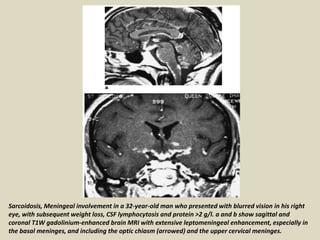

Sarcoidosis, Meningeal involvement in a 32-year-old man who presented with blurred vision in his right

eye, with subsequent weight loss, CSF lymphocytosis and protein >2 g/l. a and b show sagittal and

coronal T1W gadolinium-enhanced brain MRI with extensive leptomeningeal enhancement, especially in

the basal meninges, and including the optic chiasm (arrowed) and the upper cervical meninges.